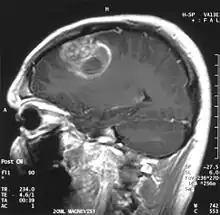

When viewed with MRI, glioblastomas often appear as ring-enhancing lesions. The appearance is not specific, however, as other lesions such as abscess, metastasis, tumefactive multiple sclerosis, and other entities may have a similar appearance.[63] Definitive diagnosis of a suspected GBM on CT or MRI requires a stereotactic biopsy or a craniotomy with tumor resection and pathologic confirmation. Because the tumor grade is based upon the most malignant portion of the tumor, biopsy or subtotal tumor resection can result in undergrading of the lesion. Imaging of tumor blood flow using perfusion MRI and measuring tumor metabolite concentration with MR spectroscopy may add diagnostic value to standard MRI in select cases by showing increased relative cerebral blood volume and increased choline peak, respectively, but pathology remains the gold standard for diagnosis and molecular characterization.

Distinguishing glioblastoma from high-grade astrocytoma is important. These tumors occur spontaneously (de novo) and have not progressed from a lower-grade glioma, as in high-grade astrocytomas[6] Glioblastomas have a worse prognosis and different tumor biology, and may have a different response to therapy, which makes this a critical evaluation to determine patient prognosis and therapy.[47][64] Astrocytomas carry a mutation in IDH1 or IDH2, whereas this mutation is not present in glioblastoma. Thus, IDH1 and IDH2 mutations are a useful tool to distinguish glioblastomas from astrocytomas, since histopathologically they are similar and the distinction without molecular biomarkers is unreliable.[48] IDH-wildtype glioblastomas usually have lower OLIG2 expression compared with IDH-mutant lower grade astrocytomas.[65] In patients aged over 55 years with a histologically typical glioblastoma, without a pre-existing lower grade glioma, with a non-midline tumor location and with retained nuclear ATRX expression, immunohistochemical negativity for IDH1 R132H suffices for the classification as IDH-wild-type glioblastoma.[62] In all other instances of diffuse gliomas, a lack of IDH1 R132H immunopositivity should be followed by IDH1 and IDH2 DNA sequencing to detect or exclude the presence of non-canonical mutations.[62] IDH-wild-type diffuse astrocytic gliomas without microvascular proliferation or necrosis should be tested for EGFR amplification, TERT promoter mutation and a +7/–10 cytogenetic signature as molecular characteristics of IDH-wild-type glioblastomas.[62]